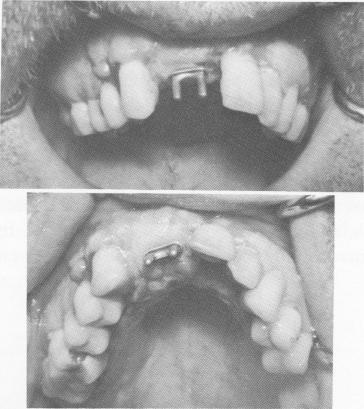

Fig. 12-93. The implant was locked tightly to the bone when the lingual extensions of the transfixation pins were "riveted" to the lingual peripheral border of the substructure by grinding them flat with a heatless stone.

Fig. 12-94. The tissues were sutured to cover the implant and to closely adapt around the protruding post.